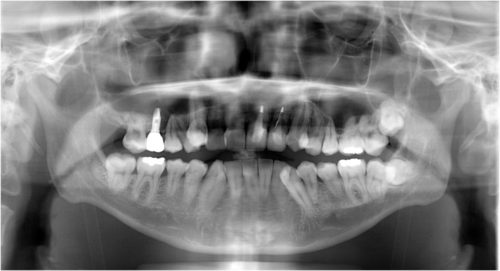

同パノラマ写真